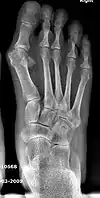

- For severe bunion deformity correction (Fig. 7)

- For recurrence correction after osteotomy procedure (Fig. 8)

Late deformity recurrence can happen after osteotomy (bone-breaking) procedures because osteotomy surgeries do not specifically stabilize first metatarsal bone.